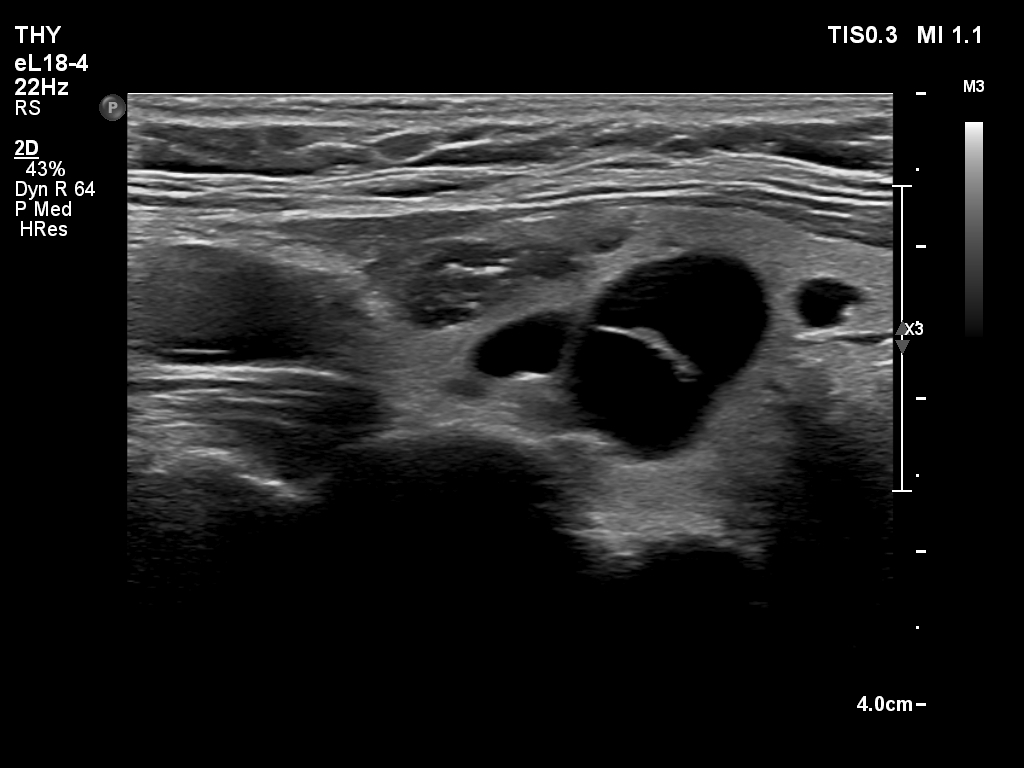

Ultrasonography. The thyroid was echonormal and had multiple nodules. There were cystic areas, an almost completely cystic nodule, and a dominantly solid nodule in the right lobe. The left lobe had three lesions. The upper solid lesion was the one we treated 16 years ago. The middle lesion was a dominantly solid while the lower one seemed to be a pure cyst. The dimensions of the nodule which has been treated with sclerotherapy were 10x11x13 mm (width, depth and length, respectively). There was a large cystic nodule in the upper pole of the left lobe. The lesion showed relatively large hyperechogenic granules. There were multiple enlarged lymph nodes lateral to the left lobe, two of largest were cystic.

After removing 4 mL fluid from the lowest lesion in the left lobe, the lesion has disappeared, which proves that this was a pure cyst. Cytology resulted in cystic degeneration.